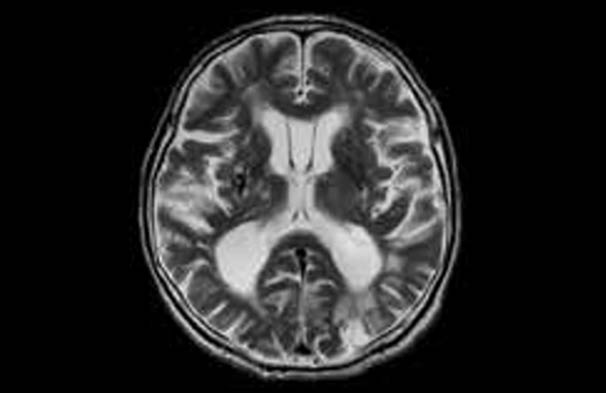

MRA와 MRI는 모두 자기 공명 현상을 이용하여 인체의 내부 구조를 촬영하는 비침습적인 의료 영상 기술입니다. 하지만 이 두 가지는 그 촬영 목적과 방법에서 큰 차이를 보입니다. 먼저, MRI는 인체의 다양한 조직을 상세하게 시각화하는 데 초점을 맞추고 있습니다. 이는 주로 뇌, 척수, 관절, 그리고 복부 장기 등을 평가하는데 사용됩니다. MRI는 강력한 자석과 전자기파를 이용해 인체 내부의 수소 원자의 반응을 기록하여 이미지를 생성합니다. 이는 고해상도의 이미지를 제공하여 전문가들이 각종 질병이나 이상을 진단하는 데 매우 유용합니다.

MRI는 인체 내부의 조직을 정밀하게 진단하기 위해 설계된 의료 영상 기술입니다. MRI의 가장 두드러진 특징은 다양한 조직의 차별적 이미징이 가능하다는 점입니다. 예를 들어: 신경 조직, 근육, 뼈, 지방 등 다양한 조직을 일정 수준 이상으로 구별하여 보여주는 것이 가능합니다. 이로써 MRI는 다양한 질병의 조기 진단 및 치료 경과 모니터링에 큰 도움이 됩니다.

- 뇌질환 평가: MRI는 뇌 tumors, 신경계 질환 및 인지 장애를 평가하는 데 최고의 진단 도구로 자리잡았습니다.